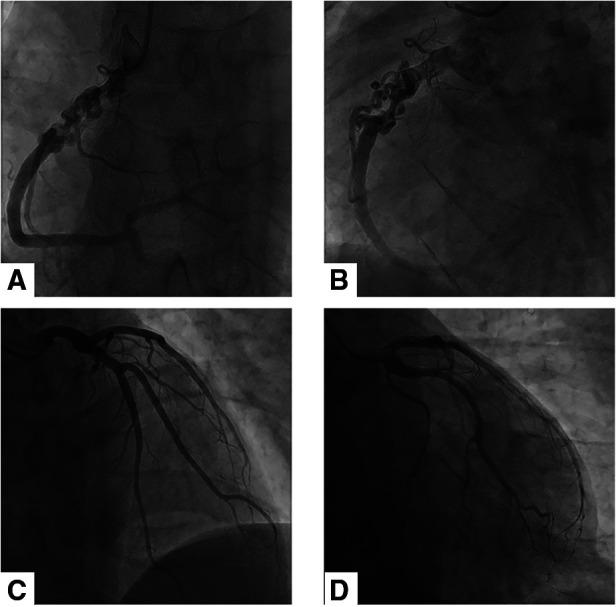

Braid-like coronary artery is very rare. It is featured by the division of the coronary artery into multiple tortuous small channels that later converge into a normal lumen at any segment of the coronary artery. We presented a case of a 27-year-old male patient with occasional chest pain. In coronary CT angiography (CCTA) and coronary angiography, a braid-like appearance was found in the right coronary artery. After multidisciplinary discussion, it was speculated to be a woven coronary artery (WCA). We conducted a literature review about woven coronary arteries.

辫状冠状动脉非常罕见。其特征是冠状动脉分成多个迂曲的小通道,这些小通道随后在冠状动脉的任何节段汇入正常管腔。我们报告了一例27岁男性患者,其偶发胸痛。在冠状动脉CT血管造影(CCTA)和冠状动脉造影中,右冠状动脉发现有辫状表现。经过多学科讨论,推测为编织状冠状动脉(WCA)。我们对编织状冠状动脉进行了文献综述。